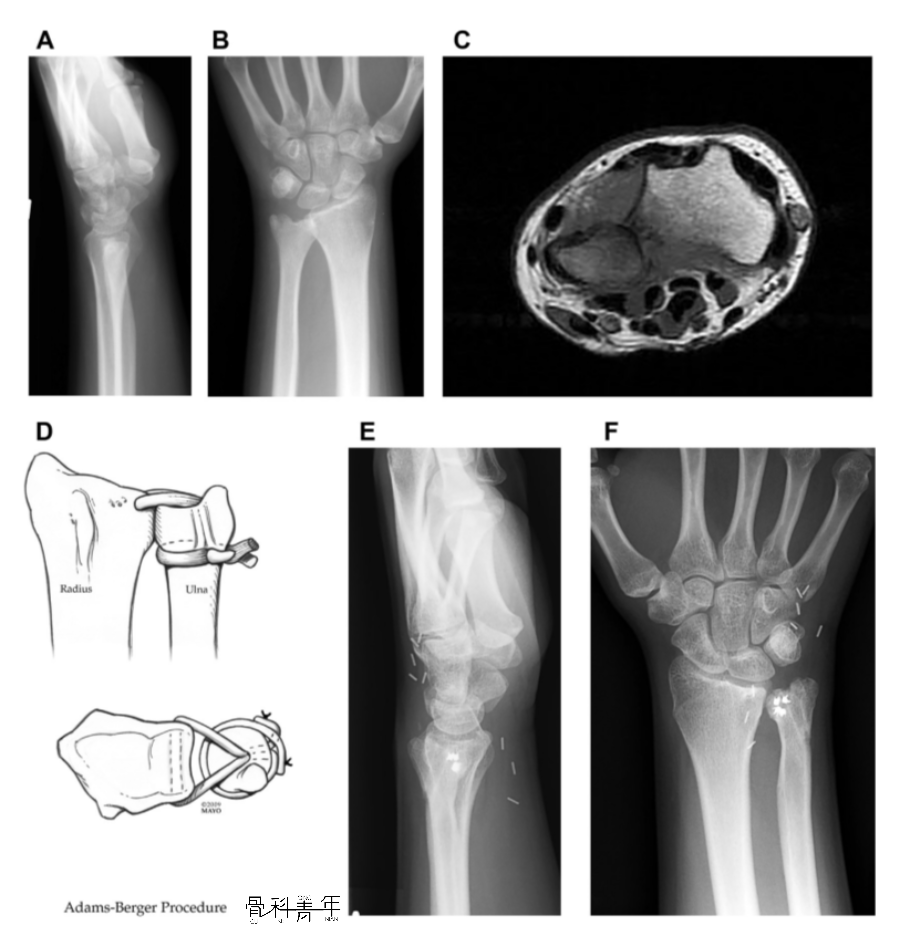

一例17岁患者,腕关节慢性疼痛3月,X线未见明显脱位(AB),MR检查提示下尺桡关节背侧脱位(C),予以下尺桡关节韧带重建(D),术后10年复查下尺桡关节位置良好,患腕无明显疼痛。